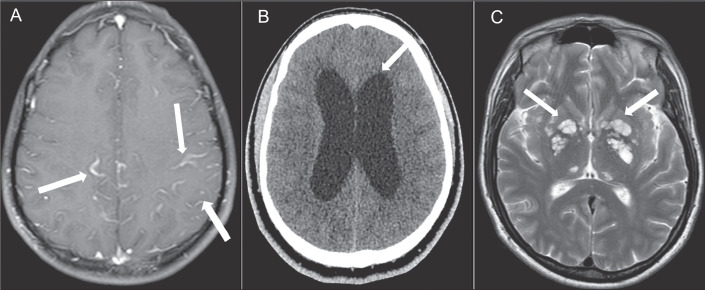

This study involved a retrospective analysis of nine cases of neurocryptococcosis (eight from our institution and one from another institution) seen between May 2014 and May 2022, together with a systematic review of the literature indexed in the PubMed, Embase, and Lilacs databases. Clinical and radiological features of those cases were further refined via an additional comprehensive literature review. The following search string was employed: cryptococcosis AND central nervous system AND (magnetic resonance imaging OR X-ray computed tomography). The search was limited to articles published between July 1978 and May 2022. Two authors, working independently, searched for and selected studies that met the inclusion criteria, and another author reviewed conflicts in a blinded manner. We used Rayyan.ai software to organize the studies, and the review was structured in accordance with the 2020 Preferred Reporting Items for Systematic reviews and Meta-Analyses guidelines. Understanding the prevalence of different patterns of neurocryptococcosis is crucial for improving diagnosis and supporting decision-making in clinical practice. Our review of the literature demonstrated that imaging examinations are a valuable resource for early diagnosis, as well as for assessment of the initial extent and pattern of the disease.